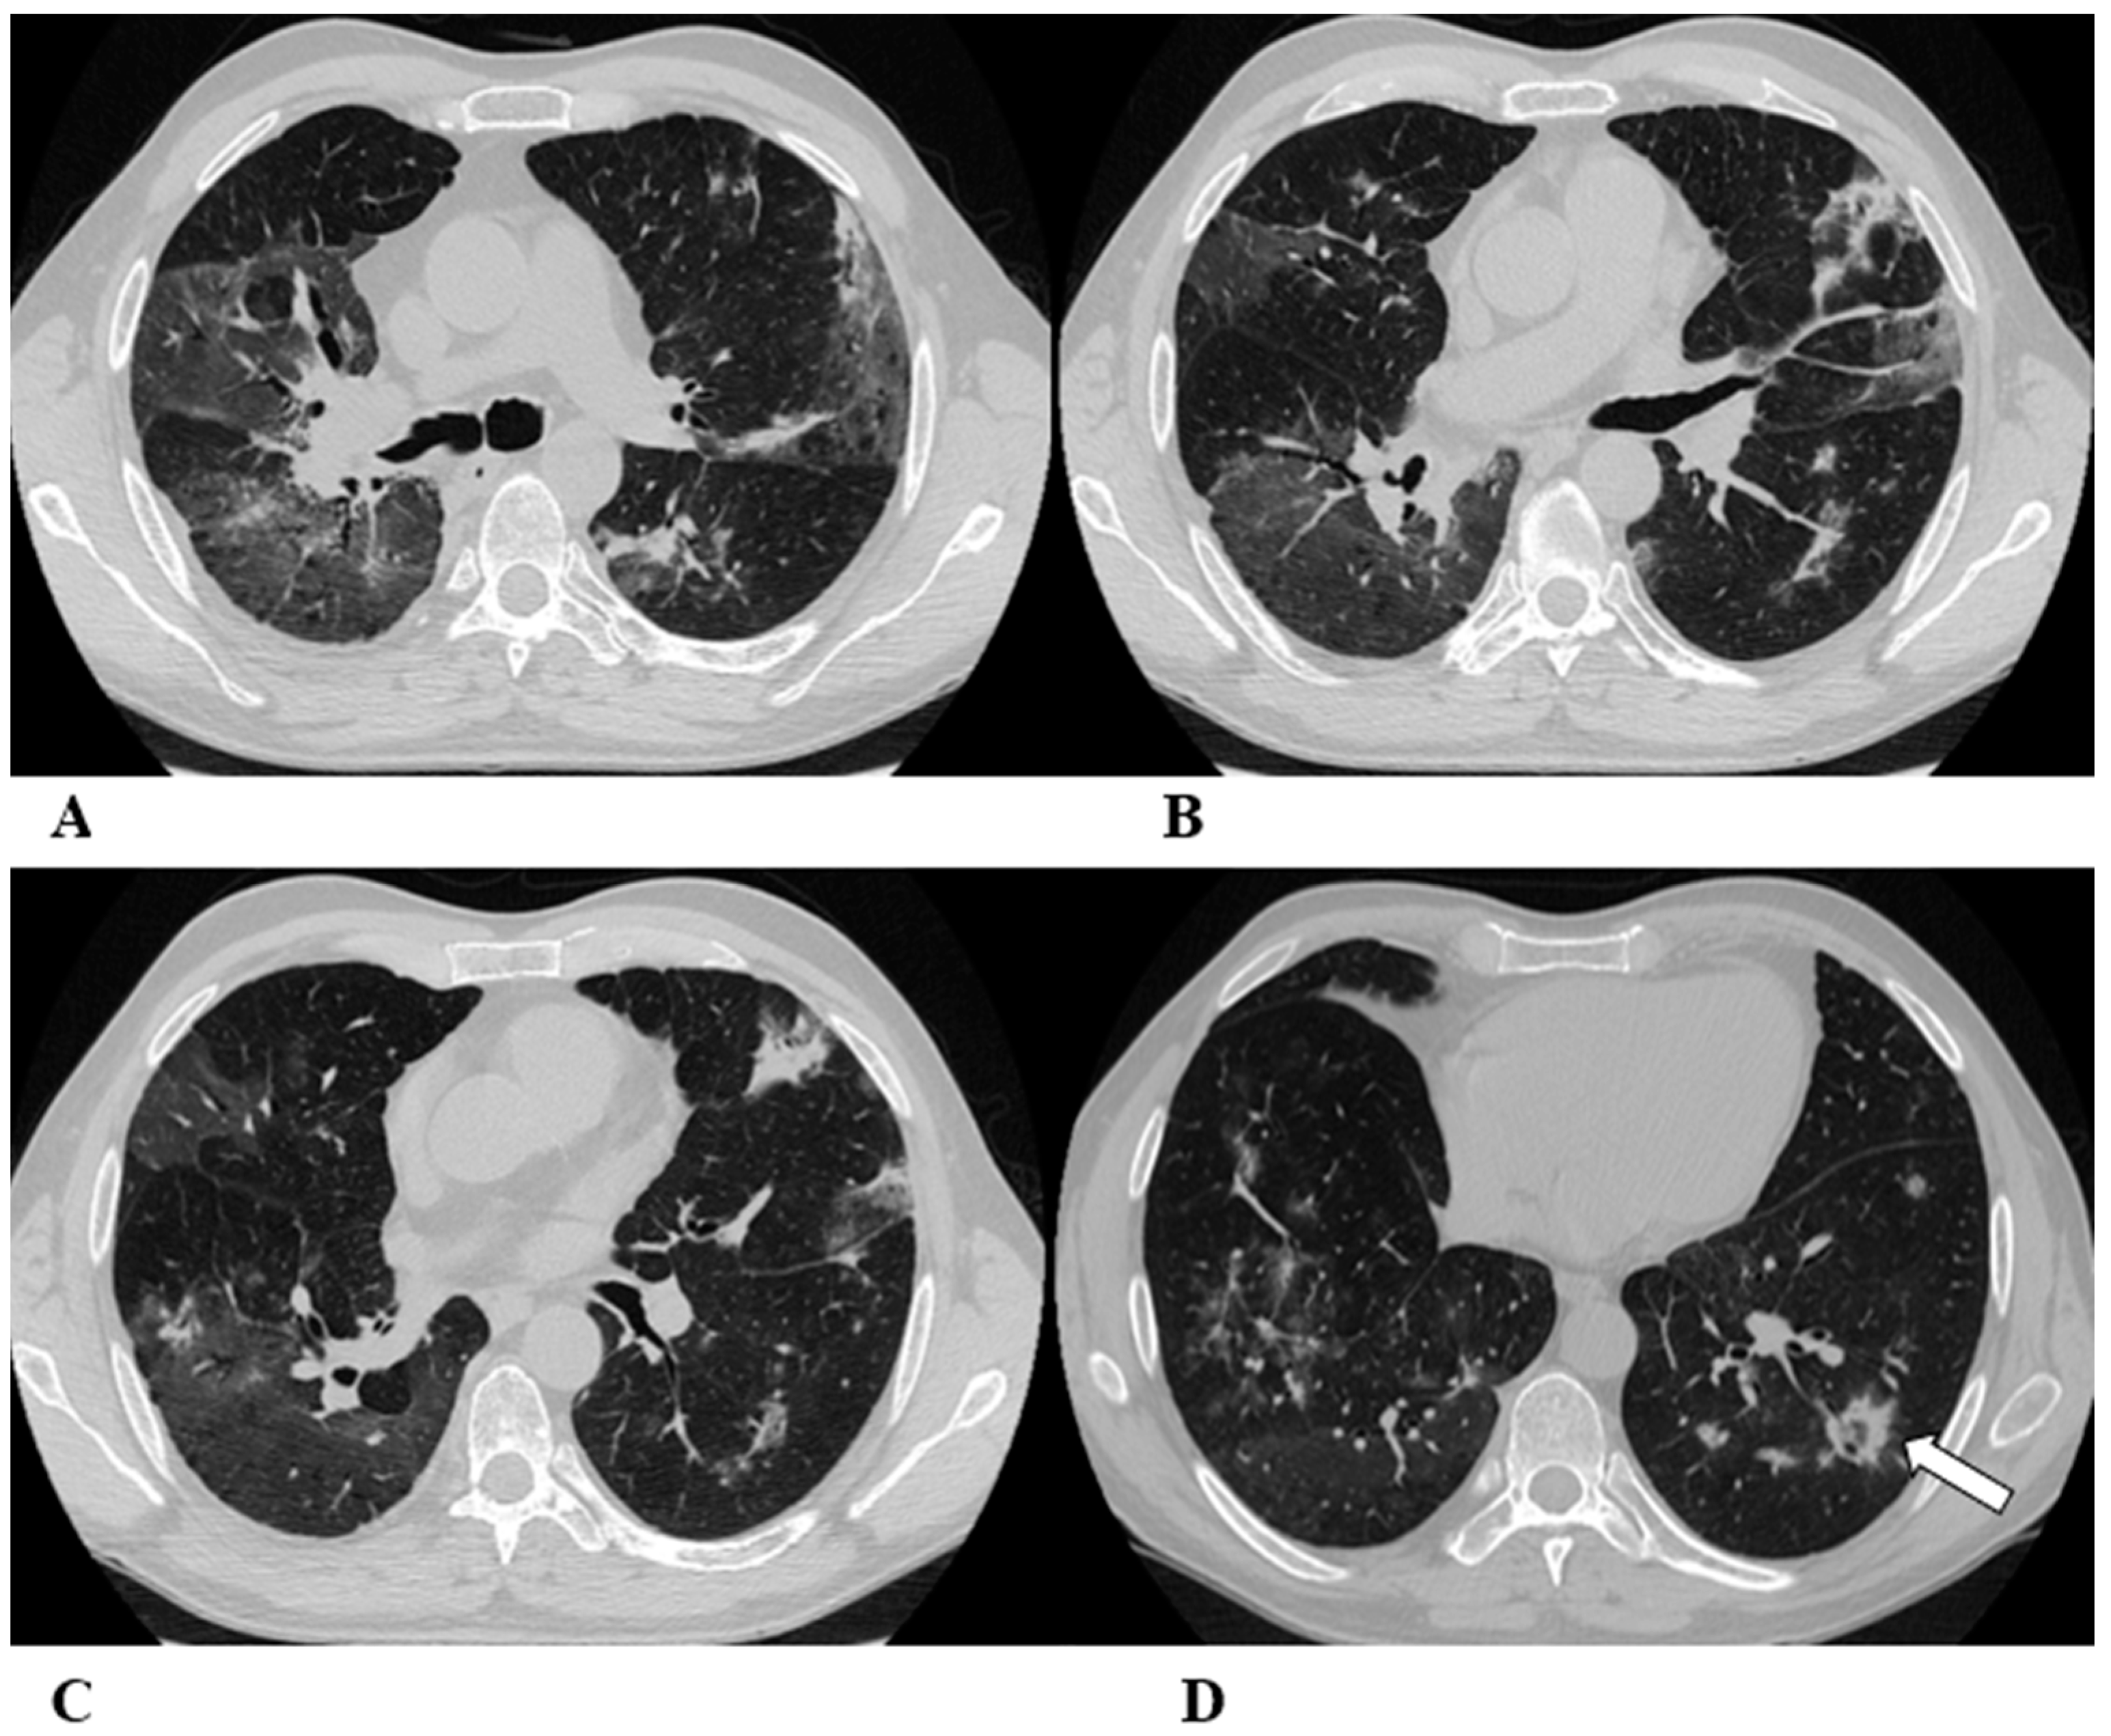

Figure 3.

Hypersensitivity pneumonia (HP). Hypersensitivity pneumonia is characterized by lymphocyte infiltrates that thicken the alveolar septa, with poorly formed non-necrotizing granulomas and multinucleated giant cells.

Typical HRCT features of acute HP are multiple bilateral small centrilobular nodules with upper lung zone predominance, lobular areas of decreased attenuation and vascularity suggestive of “air trapping” and patchy and/or diffuse GGO areas [9,12,17]. Chronic HP shows a typical “three density pattern” characterized by bilateral and diffuse lobular areas of decreased attenuation (air-trapping areas), patchy areas of real GGO in a predominant peribronchovascular distribution with traction bronchiectasis and bronchiolectasis inside (fibrosis signs), and also areas of a relative increase in density related to the normal CT appearance of the lung (GGO-like areas).

The ICI-associated HP pattern is indistinguishable from that of HP induced by allergen exposure. For this reason, in addition to the exclusion of atypical pneumonia, accurate exposure history is essential for the correct evaluation of the patient.

(A–D) A 76-year-old woman with colorectal cancer who received nivolumab and ipilimumab as second-line treatment. Seven months later, the patient presented worsening cough and dyspnea, along with weight loss, but she was able to undergo HRCT examination just two months after the onset of symptoms.

Axial chest CT scans of the upper lobes (A,B) show patchy GGO areas (black arrowheads) with over-imposed reticulation in a predominant peribronchovascular distribution and early traction bronchiectasis (black arrow).

Bilateral areas of decreased attenuation (air trapping) (white arrows) with geometric morphology are easily recognizable in both the inspiratory (A,B) and expiratory (C,D) acquisitions.